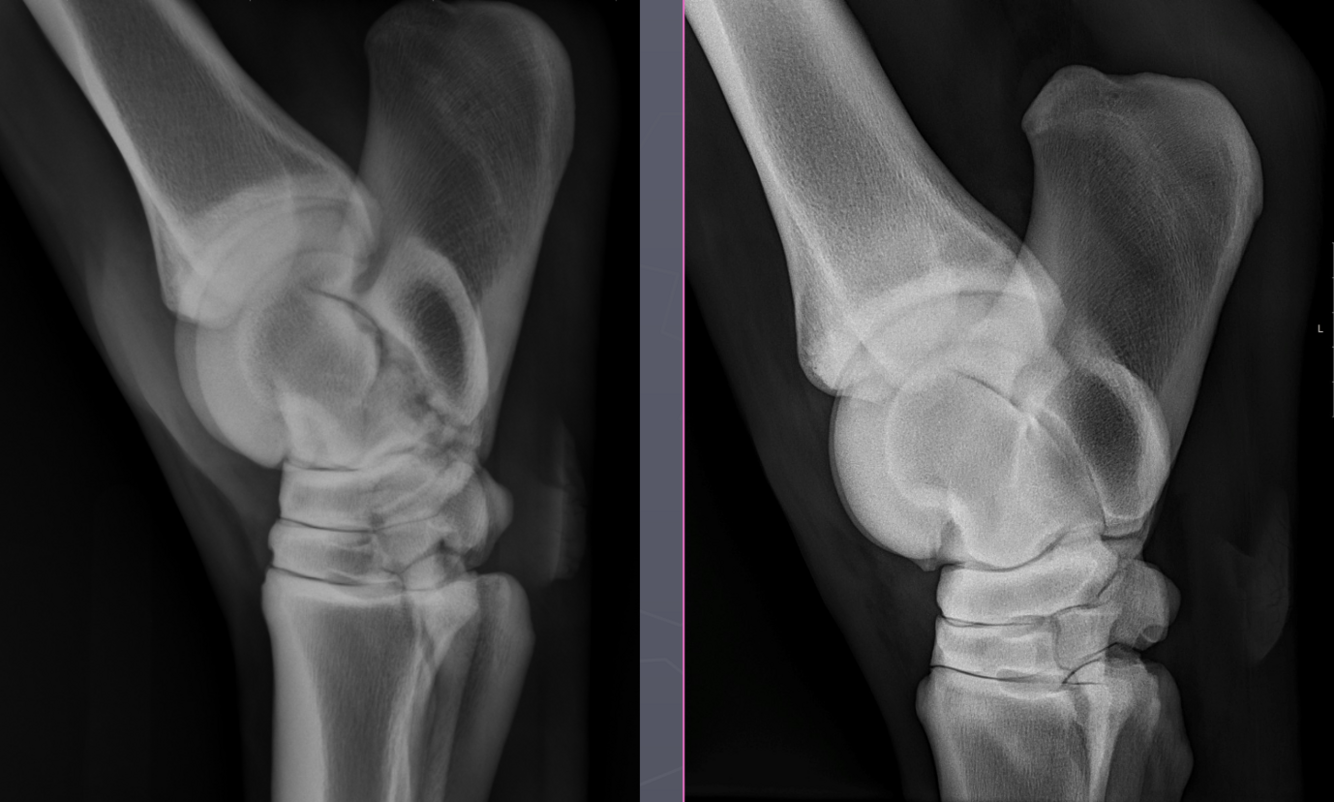

What is shown in these images?

A

tarsal bone collapse; early stage